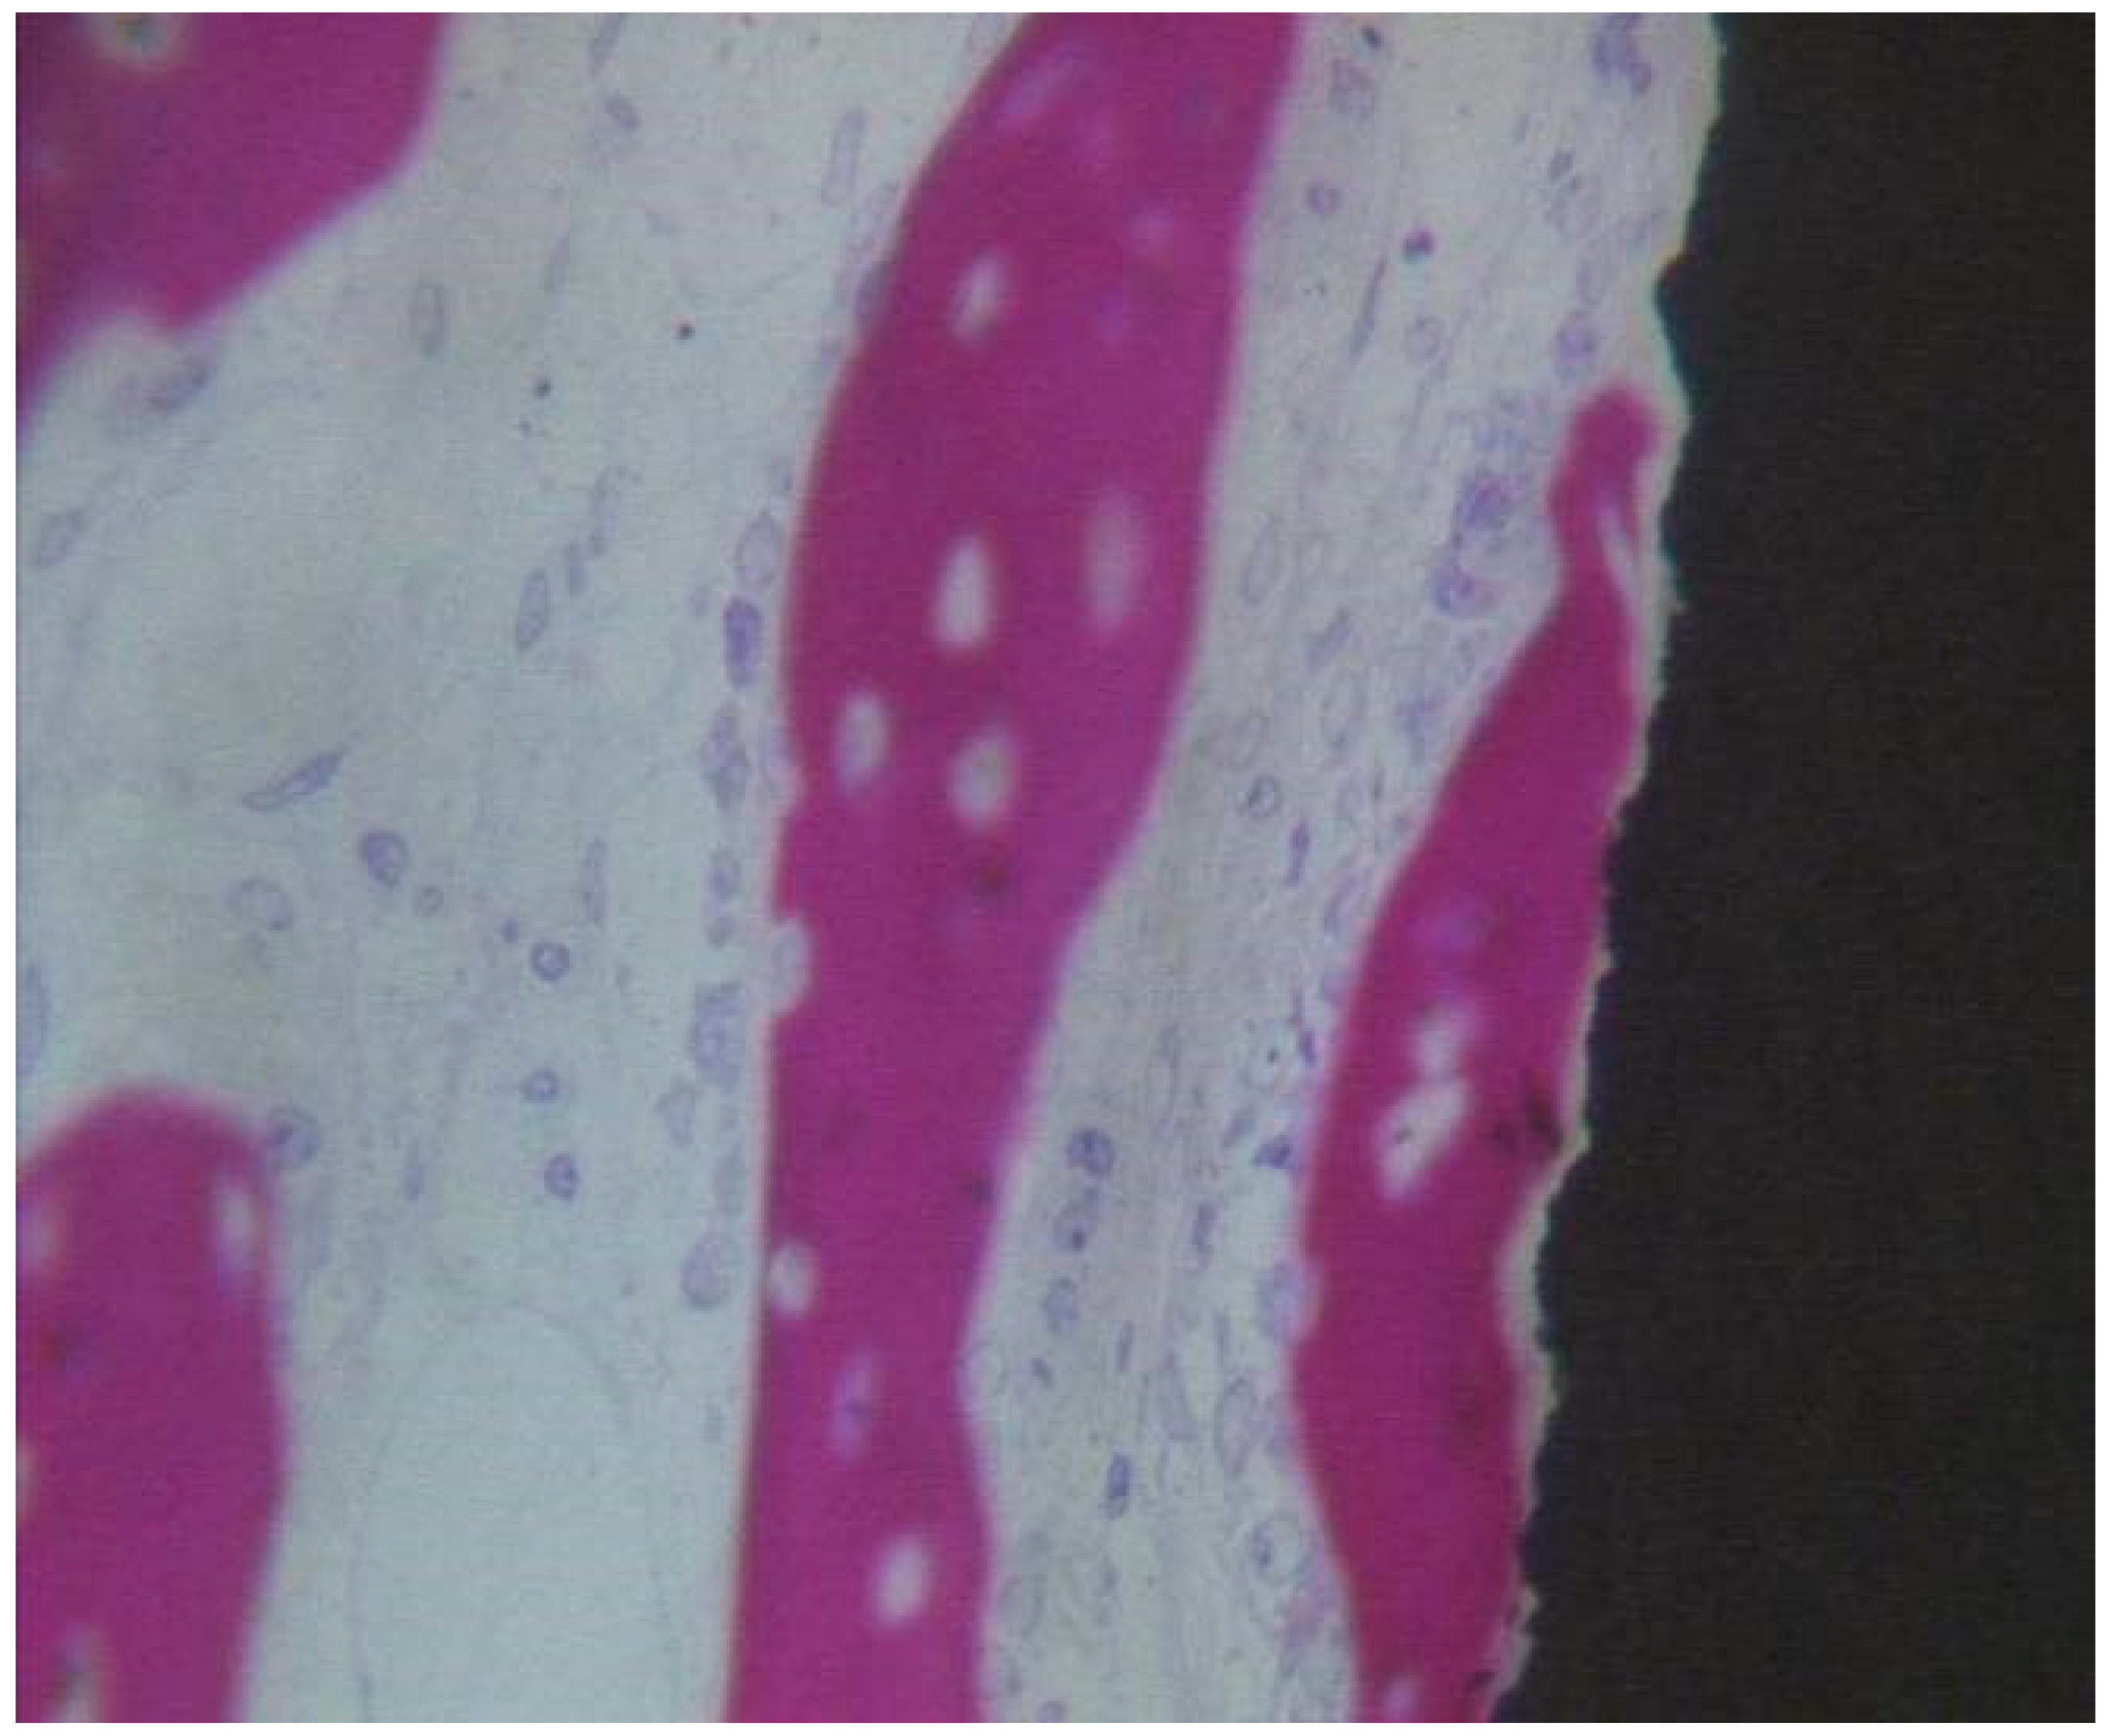

Coated Implant Surface

In close contact to the dental implant surface there were many newly formed bone trabeculae (Figure 9). Osteoblast cells were observed depositing the osteoid matrix on the implant surface. BD was 15.5 ± 0.9% and BIC was 21.5 ± 2.3%, bone area inner threads (BAIT) was 23 ± 0.5%, and bone area outer threads (BAOT) was 19 ± 0.3%.

Figure 9.

Newly formed bone observed in direct contact to the implant surface. The osteocyte lacunae were large. No evidence of inflammatory cells was present. Many osteoblasts were present, depositing the osteoid matrix. Acid fuchsin-toluidine blue 200×.